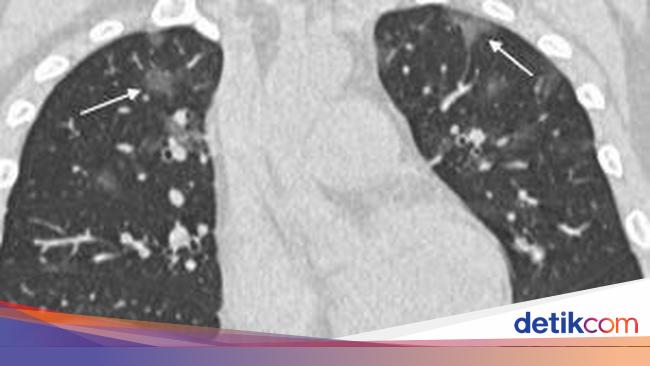

Gambar Hasil X Ray Penderita Virus Corona Timbulkan Bercak Putih Di Paru Paru Pikiran Rakyat Bekasi

Mau Tahu Hasil Rontgen Paru Pasien Covid 19 Seperti Apa Klik Di Sini Semua Halaman Grid Health

Hasil Rontgen Covid 19 Seperti Apa Berbahayakah Bila Paru Memutih

Dokter Ungkap Kondisi Paru Pasien Covid 19 Gejala Berat Ini Penampakannya Info Sehat Fkui

Beginikah Penampakan Paru Paru Yang Terinfeksi Virus Corona Covid 19

Cara Baru Deteksi Virus Corona Dengan Ct Scan Paru Paru

Mengenal Ground Glass Opacity Hasil Rontgen Paru Putih Akibat Covid